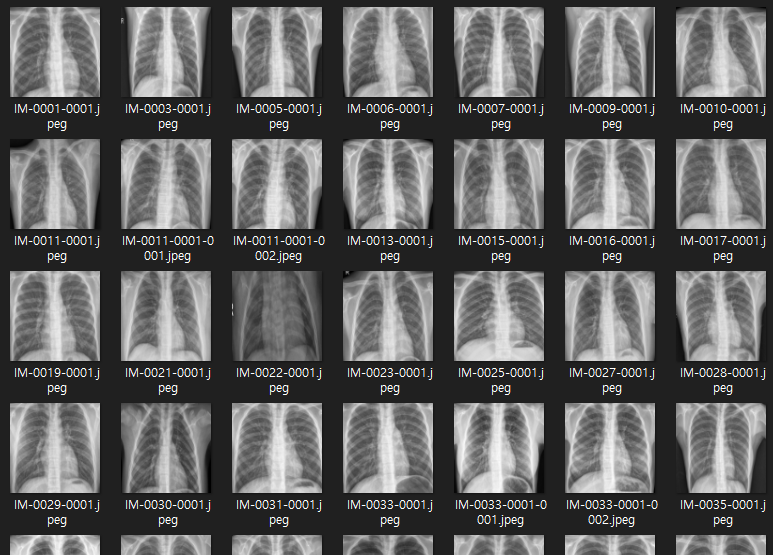

2020년 10월 6일 기준 본 데이터셋은 train, test, val폴더로 이루어져 있으며 각 폴더마다 NORMAL(정상)과 PNEUMONIA(폐렴)로 구분되어 있다.

데이터는 모두 .jpeg이미지이며 크기가 모두 다르다.

또한 사진이 기울어진 경우도 있으며 사진의 중심과 환자의 중심이 일치하지 않은 경우도 다수 있다.

데이터 셋을 살펴보면 사진의 크기가 모두 다르고 흉부의 위치도 조금씩 다르다.

데이터 하나하나 필요한 영역만 잘라내고 크기를 조절하는 것은 매우 비효율적인 작업이기에 python과 opencv를 이용하여 필요한 영역만 잘라내고 크기를 조절해주는 프로그램을 만들었다.

이미지를 잘라내고 크기를 224* 224로 조절했다. 이 과정에서 일부 이미지가 상하로 늘어난 모습이 되었다.

이미지 전처리 실행 결과

필요한 영역만을 가지며, 크기가 일정한 데이터셋이 만들어졌다.